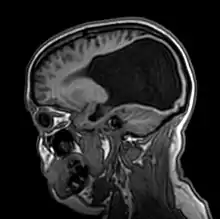

Colpocephaly is characterized by disproportionately large occipital horns of the lateral ventricles (also frontal and temporal ventricles in some cases). MRI and CT scans of patients demonstrate abnormally thick gray matter with thin poorly myelinated white matter. This happens as a result of partial or complete absence of the corpus callosum. Corpus callosum is the band of white matter connecting the two cerebral hemispheres. The corpus callosum plays an extremely important role in interhemispheric communication, thus lack of or absence of these neural fibers results in a number of disabilities.[12]

The lemon sign on CT scans of patients refers to the shape of the fetal skull when the frontal bones lose their normal convex contour and appear flattened or inwardly scalloped. This gives the skull a shape similar to that of a lemon. The sign is seen on transverse sonograms of the fetal cranium obtained at the level of the ventricles. A special case is found in literature where lissencephaly, colpocephaly, and septal agenesis are all present together. The CT scans of the patient shows the ventricular system having a unique appearance of a crown of a king. This is referred to as the 'CROWN SIGN'.[8]

Diagnosing colpocephaly prenatally is difficult because in many cases signs start to appear after birth. Prenatal diagnosis is made by detecting enlargement of either or both occipital horns of the lateral ventricles. Usually prenatal ultrasounds don't show cephalic abnormalities and in cases that they do show abnormality is of low accuracy, making it difficult to diagnose colpocephaly. Often, abnormalities in prenatal ultrasounds can be misdiagnosed as hydrocephalus.[2]

Postnatal

After birth, MR imaging can be done to look for cephalic abnormalities. This is the most commonly used method for diagnosing colpocephaly. Physicians look for abnormally large occipital horns of the lateral ventricles and diminished thickness of white matter.[12] Spinal tapping is not a preferred method for diagnosis because newborn babies with colpocephaly or hydrocephaly have open fontanelles which makes it difficult to collect CSF. Also, colpocephaly is not associated with increased pressure.[13]